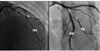

La figure 1 illustre des exemples de dissections coronaires en angiographie.

Figure 1 Images de dissection coronaire en coronarographie. À gauche : dissection coronaire sur l’artère interventriculaire antérieure avec flap intimal (flèche). À droite : dissection coronaire étendue sur l’artère interventriculaire antérieure proximale avec extension sur la première diagonale. IVA : interventriculaire antérieure ; Dg : diagonale. |

Plusieurs critères orientent vers le diagnostic de dissection coronaire spontanée [13] : (1) l’absence d’athérome sur les autres artères coronaires, (2) la présence d’un flap radiotransparent délimitant deux lumières (Figure 1), (3) une stagnation du produit de contraste dans la lumière artérielle, (4) des limites nettes de la zone anormale, souvent au niveau d’une branche collatérale, (5) une réduction longue du calibre artériel, régulière ou en aspect de sténoses multiples, mimant une silhouette de « phasme » ou de « radis ».